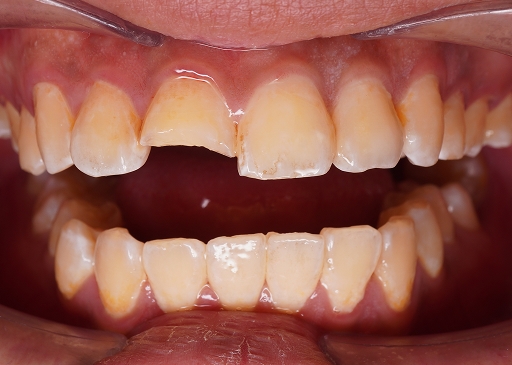

Trigger: When biting down or releasing a bite

Cause: Cracked tooth

A knocked-out tooth is a tooth that has been completely dislodged from its socket due to injury. Immediate dental care is crucial to improve the chances of saving the tooth.

We may reposition the tooth and secure it with a dental splint to stabilise it while the surrounding tissues heal.